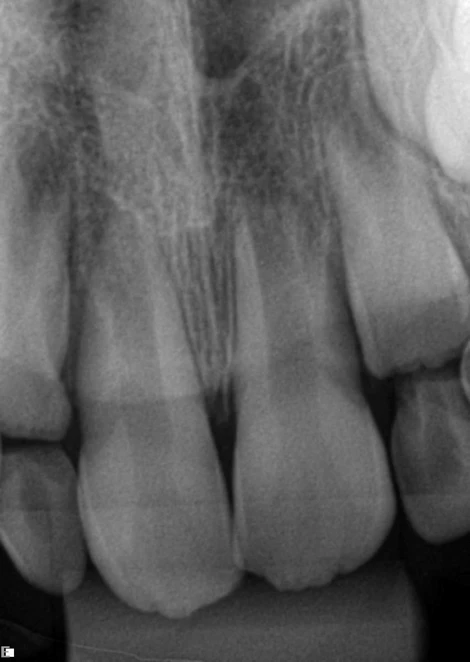

Paciente com 8 anos de idade, compareceu ao consultório com fístula em região vestibular e leve escurecimento em dente 11 (figura 1). Foi realizado o exame clinico e radiográfico (radiografia periapical) na qual foi observado o ápice aberto desse dente (figura 2). No teste de sensibilidade com gás refrigerante o dente apresentou vitalidade negativa.